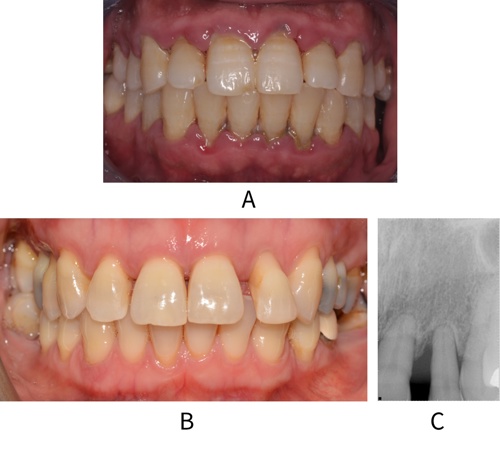

Periodontitis is characterised by the loss of gingival and periodontal tissues. Patients present with a variety of signs including interproximal recession, increased periodontal probing depths, bleeding on probing, mobility of teeth, drifting or loss of teeth and signs of infection with pus on probing. Periodontitis is a result of plaque-induced inflammation that results in loss of periodontal attachment (see figure: Periodontitis).17

A: Image of a patient with generalised periodontitis and significant gingivitis.

B: Patient with drifted tooth 22 secondary to periodontitis (image C) but no gingivitis